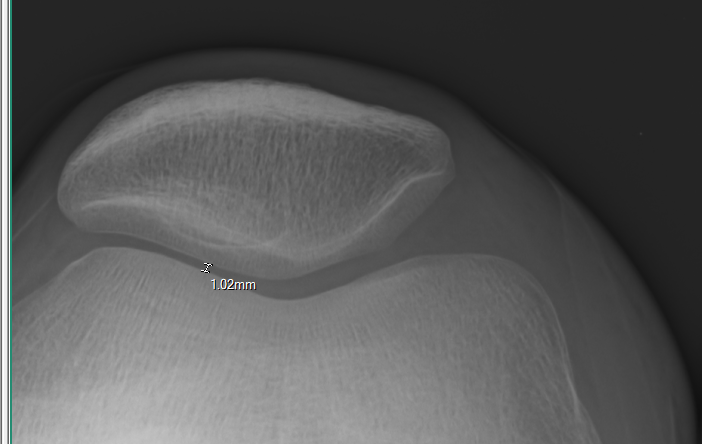

จากรูปด้านบนผมลองไป xray ดูครับ ผลก็ตามภาพ ลืมบอกไปว่าเป็นทั้ง 2 ข้างเลยครับ แต่ในรูปเป็นข้างซ้าย

จะหนักกว่าหน่อยคือระยะห่างจากรูปประมาณ 1mm เอง ส่วนด้านขวาประมาณ 4mm แต่ผมไม่รู้ว่าปรกติแล้วมันห่างกันแค่ไหน